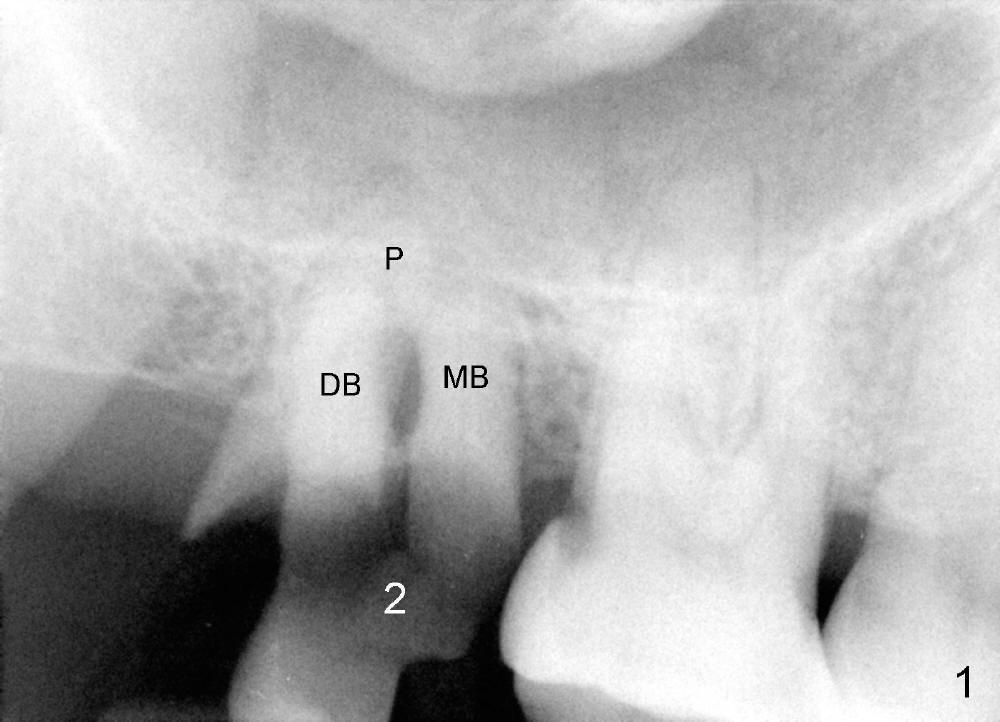

Immediately preop PA and photo confirm that the upper right 2nd molar is nonsalvageable (Fig.1,2). After extraction, it appears that there are 3 potential sites for immediate implant.

The septum is narrow buccopalatally (Fig.3 S). It is difficult to make initial drill penetration at the top of the septum. It appears that the septal bone height is limited (Fig.10a). Preop PA shows that the sinus floor is lower than the root apices (Fig.1). This is a typical sign of sinus floor ditching in between the apieces.

By contrast the palatal socket is deep and relatively small (Fig.4 P), easy to insert taps without drills. When a 7x11 mm tap is placed (Fig.5 T), the coronal end is more or less near the lingual cusps (functional cusps). Although the 7x14 mm tap (Fig.6 T) and a 7x11 mm implant (Fig.7 I) look poking into the maxillary sinus, they are in fact within the palatal socket (Fig.10c). Allograft and Osteogen are placed in the buccal socket (Fig.7 *), followed by collagen dressing (Fig.8 *). A 5x5 mm abutment is placed (Fig.8 A). An immediate provisional (Fig.9 P) is cemented to keep the graft and collagen dressing in place.